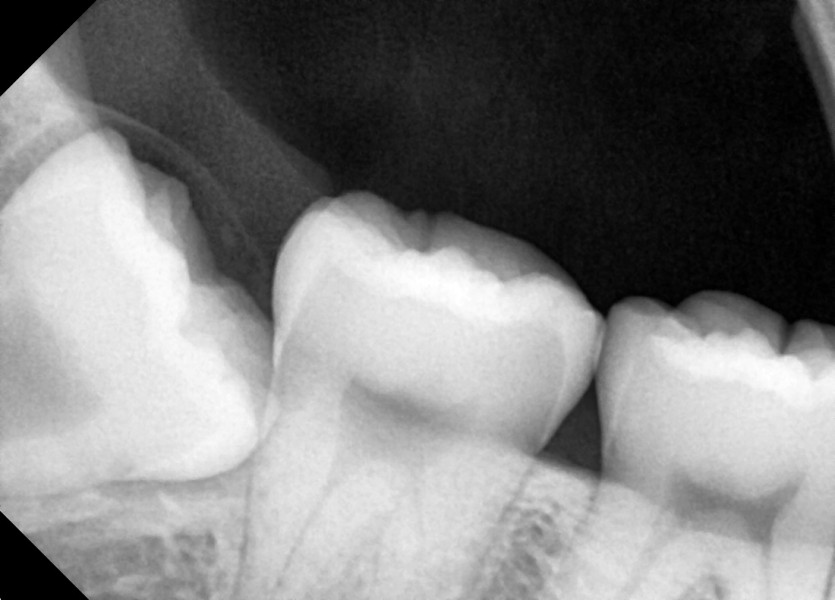

#38,48 사랑니 발치

구강 외과 전문의가 당일 발치했습니다.